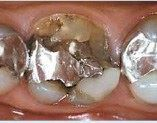

Kroner kan fremstilles i guld, rent porcelæn eller en kombination af metal og porcelæn (metalkeramik).

Guldkroner er de stærkeste og er derfor de bedste til kindtænder. Både metalkeramikkroner og porcelænskroner ligner naturlige tænder, men de er ikke helt så stærke som guldkroner.

Metalkeramikkroner består af en skal af guld, hvorpå der brændes et lag af tandfarvet porcelæn. De kan anvendes på næsten alle tænder. Ved meget lyse og gennemskinnelige fortænder er porcelænskroner dog at foretrække.